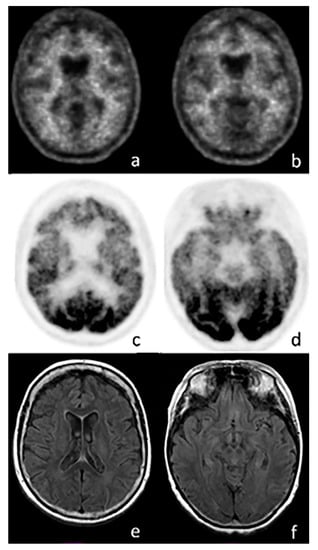

2.1. FDG Imaging in AD

3.1. FDG-PET in FTD

4.3. FDG-PET Imaging in SNCApathies

5.1. FDG-PET Imaging in Atypical Parkinsonian Syndromes